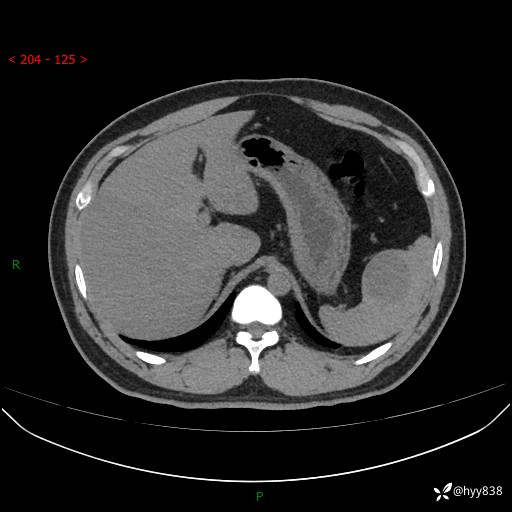

【患者信息】:31岁/男

【主诉】:超声发现脾脏肿物,为进一步诊治来我院,门诊以“脾脏占位”收入院

【检查】:上腹部CT平扫+增强